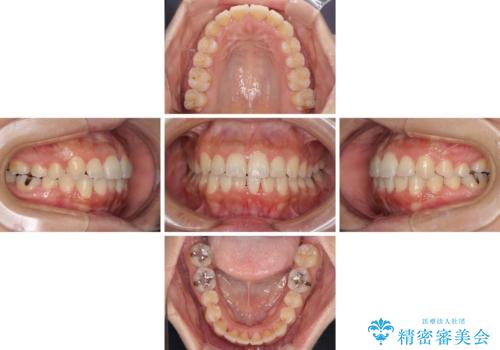

前歯のデコボコをインビザラインでスッキリと

- 上下前歯のデコボコを気にして来院された患者様です。

デコボコを解消する過程で、歯列の拡大により口元が突出する可能性があったため、4本の親知らずを抜歯しておき、歯列全体が後方に移動するように設計し、インビザラインにて矯正治療を行うこととしました。

日々の装着時間をしっかりと守って治療の臨んでくださったため、治療前のシミュレーションに近い形で矯正治療を進めて行くことができました。